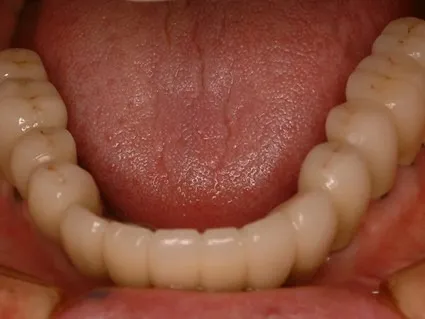

・平成20年3月8日右下34567左下34567にプラントインプラントを埋入。

・平成20年4月23日右上1234左上12345にプラトンインプラントを埋入。

・平成20年5月16日右上58左上8にプラトンインプラントを埋入。

・平成20年9月16日右上5を撤去。その後問題なく経過。